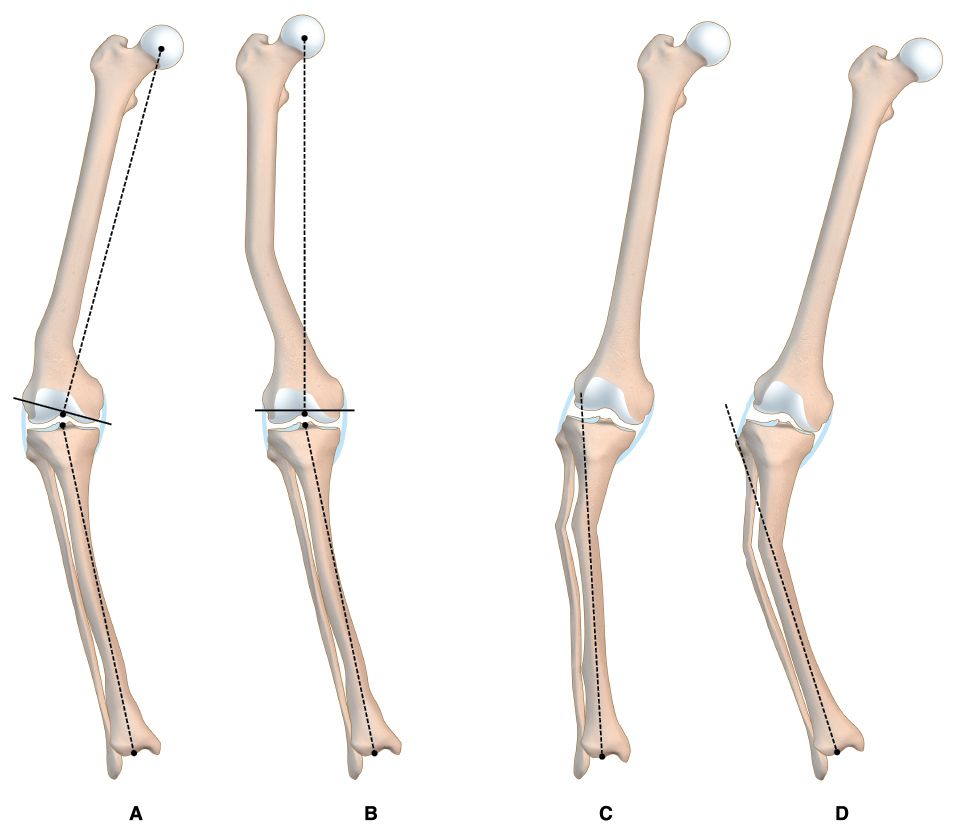

It is essential to know the aetiology of the deformity and its location regarding the knee in order to evaluate its real influence on the mechanical axis of the limb. [1], Jeffery RS, Morris RW, Denham RA Coronal alignment after total knee replacement. JBJS Br 1991;73(5):709.[3], Panayiotis JP, Karachaloios T, Themistocleous GS Total knee arthroplasty in patients with pre-existing fracture deformity. Orthopedics. 2007;30(5):373.[4] Wolff AM, Hungerford DS, Pepe CL The effect of extraarticular varus and valgus deformity on total knee arthroplasty. Clin Orthop. 1991;271:35-51. The nearer to the joint the deformity is, the more it will affect the mechanical axis and the intraarticular bone correction cuts (1/3 third rule – Figure 4).

The distal femoral bone cut can be planned using as reference the femoral mechanical axis (cut in 90°) or preferably the axis of the femur proximal to the deformity. The correction of the extra-articular deformity can be made through intra-articular cuts when the femoral distal cut line respects the MCL insertion, since on the lateral side, a lateral epicondylar osteotomy can be performed similar as when dealing with severe valgus deformities. (Figure 5 A & B). [2], Mullaji Arun, Shetty GM Computer-Assisted Total Knee Arthroplasty for arthritis with extra-articular deformity. J. Arthroplasty. 2009;24(8):1164.[3], Panayiotis JP, Karachaloios T, Themistocleous GS Total knee arthroplasty in patients with pre-existing fracture deformity. Orthopedics. 2007;30(5):373.[4], Wolff AM, Hungerford DS, Pepe CL The effect of extraarticular varus and valgus deformity on total knee arthroplasty. Clin Orthop. 1991;271:35-51.[6],Wang JW, Wang CJ Total knee arthroplasty for arthritis of the knee with extra-articular deformity. JBJS Am. 2002;84(10):1769-1774.[8], Mann JW, Insall JN, Scuderi GR Total knee arthroplasty in patients with associated extra-articular angular deformity. Orthop Trans. 1997;21:59.[15] Rand JA, Franco MG Revision considerations for fractures about the knee. In: Goldberg VM (Ed.), Controversies of total knee arthroplasty. Raven Press Ltd, New York, USA, pp. 1991;235-247.

The proximal tibial bone resection must be made at 90° to the axis of the tibial shaft distal to the deformity (Figure 5 C & D).[8], Mann JW, Insall JN, Scuderi GR Total knee arthroplasty in patients with associated extra-articular angular deformity. Orthop Trans. 1997;21:59.[2], Mullaji Arun, Shetty GM Computer-Assisted Total Knee Arthroplasty for arthritis with extra-articular deformity. J. Arthroplasty. 2009;24(8):1164.[3], Panayiotis JP, Karachaloios T, Themistocleous GS Total knee arthroplasty in patients with pre-existing fracture deformity. Orthopedics. 2007;30(5):373.[15] Rand JA, Franco MG Revision considerations for fractures about the knee. In: Goldberg VM (Ed.), Controversies of total knee arthroplasty. Raven Press Ltd, New York, USA, pp. 1991;235-247. The use of guides is ruled by the same principles as for the femur.[6]Wang JW, Wang CJ Total knee arthroplasty for arthritis of the knee with extra-articular deformity. JBJS Am. 2002;84(10):1769-1774. A difference is that an “unusual” cut of the tibia generates an asymmetrical gap for the extension and flexion gap equal, which makes these deformities easier to correct through a proper soft tissue release. Nevertheless, there is controversy about the severity of the deformity in which the correction must be performed with an extra-articular osteotomy. [2], Mullaji Arun, Shetty GM Computer-Assisted Total Knee Arthroplasty for arthritis with extra-articular deformity. J. Arthroplasty. 2009;24(8):1164.[3], Panayiotis JP, Karachaloios T, Themistocleous GS Total knee arthroplasty in patients with pre-existing fracture deformity. Orthopedics. 2007;30(5):373.[4], Wolff AM, Hungerford DS, Pepe CL The effect of extraarticular varus and valgus deformity on total knee arthroplasty. Clin Orthop. 1991;271:35-51.[10], Radke S, Radke J Total knee arthroplasty in combination with a one-stage tibial osteotomy. Journal of Arthroplasty. 2002;17(5):533.[11], Windsor RE, Insall JN, Vince KG Technical considerations of total knee arthroplasty after proximal tibial osteotomy. JBJS Am. 1988;70(4):547.[16] Ritter MA, Faris GW Total knee replacement following extra-articular deformities. Orthopedics 2003;26:969.In patients with multiplanar or complex deformities, this possibility is more evident. In case of extra-articular osteotomy combined with TKA in a single stage procedure, the method used to stabilize the osteotomy must be defined. We prefer, if possible, to use femoral or tibial stems instead of plates and screws.